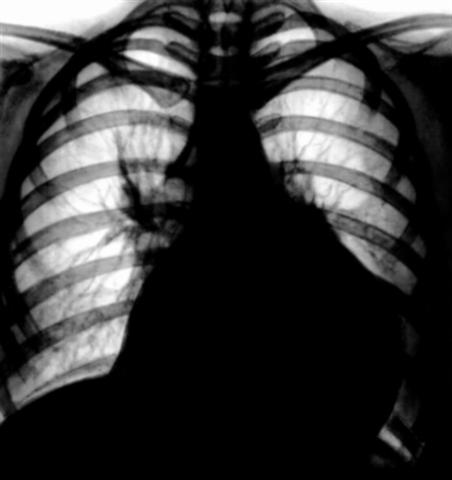

Рис. 2. Рентгенограмма грудной клетки больного экссудативным перикардитом: тень сердца увеличена в поперечном размере, дуги плохо дифференцируются, форма сердца трапециевидная.